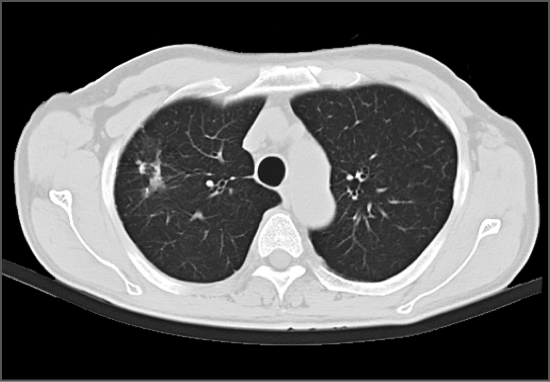

有研究发现CT对早期肺癌的敏感度是胸片的4-10倍,早期肺癌干预后5年生存率约为85-90%。16排及以上CT机的扫描辐射剂量降低但发现病变的能力不变,有效剂量小于1mSv,远低于世界平均本底辐射3mSv。16排及以上CT机可以发现0.1-0.5cm病变,可以准确显示肺内病变的细微结构和边缘特征。

胸部CT扫描经常可以发现肺内的小结节灶,肺内间质、实质性病变均可以得到较好的显示。采用增强扫描以明确纵隔和肺门有无肿块或淋巴结增大、支气管有无狭窄或阻塞,对原发和转移性纵隔肿瘤、淋巴结结核、中心型肺癌等疾病的诊断,均有很大价值。